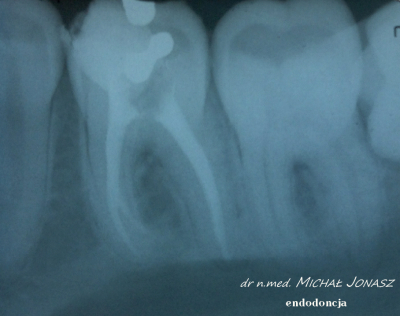

Zmiany okołowierzchołkowe to ogniska zniszczenia kości wokół wierzchołków korzeni zębów. Przewlekłe, nieleczone zmiany zapalne w obrębie korzeni zęba mogą powodować duże uszkodzenia kości i skutkować utratą zębów. Reendo polega na usunięciu materiału, którym wypełnione są kanały i zlokalizowaniu nieprawidłowości, czyli niedostatecznie oczyszczonego lub wypełnionego kanału albo pozostawionego, złamanego narzędzia w jego świetle. Dzięki mikroskopowi problemy anatomiczne, takie jak wąskie, zarośnięte kanały, zakrzywione korzenie, boczne, nietypowe odnogi są możliwe do wyeliminowania.

Diagnostyka obrazowa i wprawne oko Stomatologa są podstawą do podjęcia powtórnego leczenia kanałowego. Wychwycenie zmian patologicznych kierujących na powtórne leczenie kanałowe często jest efektem wnikliwej analizy zdjęć RTG. Powtórnego leczenia kanałowego wymagają zęby, których kanały korzeniowe nie zostały prawidłowo wypełnione. Im dłuższy czas upływa od zakończenia pierwotnego leczenia kanałowego, tym mniejsza szansa, że ząb da o sobie ponownie znać. Nieprawidłowo przeleczony kanałowo ząb, to potencjalnie ogromne ryzyko dla pacjenta. Ząb źle leczony kanałowo przypomina o sobie po wielu latach, bądź w postaci dolegliwości bólowych, bądź przez wolno, bezobjawowo rozwijającą się torbiel. Wytworzenie się torbieli wymaga już interwencji z zakresu chirurgii stomatologicznej. W takiej sytuacji po leczeniu powtórnym pacjent jest kierowany do chirurga na zabieg wyłuszczenia torbieli.

Na zdjęciu RTG efekt leczenia endodontycznego można ocenić po 3 – 6 miesiącach. Każde kanałowe leczenie należy systematycznie kontrolować poprzez wykonywanie rutynowych zdjęć radiologicznych, tak by zawczasu uniknąć nieprzyjemnych problemów.